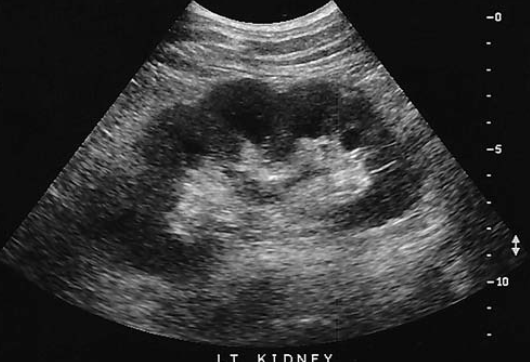

which congenital anomaly is identified in this kidney

fetal lobulation